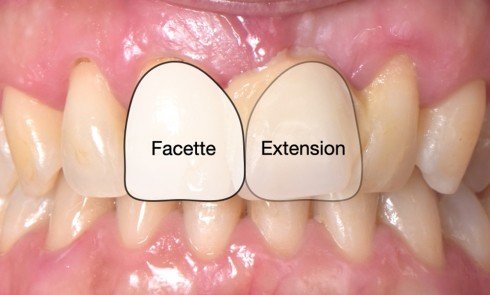

• Traitement micro invasif : il s’agit essentiellement de l’érosion/infiltration (fig. 5), mais une alternative peut également être utilisée pour les mêmes indications : le traitement de micro abrasion (fig. 6). L’indication première de cette technique est d’arrêter la progression des lésions carieuses non cavitaires lors d’une déminéralisation de l’émail (ICDAS 2) ou cavitaires au niveau de l’émail sans déminéralisation de la dentine sous-jacente (ICDAS 3) d’un patient à faible risque carieux.

Le principe d’érosion infiltration consiste à infiltrer par capillarité l’émail déminéralisé avec de la résine. La surface dentaire doit être préalablement traitée par un acide afin d’ouvrir les porosités de surface de l’émail et permettre une meilleure pénétration de la résine. Le processus carieux sera stoppé en bloquant la pénétration des acides cariogènes et la structure dentaire sera préservée.

Cette technique est réalisée en une seule séance clinique, et présente l’avantage d’être peu invasive et indolore. Cependant, le problème de l’accessibilité dans les lésions proximales est un facteur qui limite l’utilisation de ces thérapeutiques. Le recours à un élastique orthodontique quelques jours avant la mise en place de la résine est une solution intéressante pour améliorer l’accessibilité et traiter les lésions de déminéralisation en proximal. Aujourd’hui, ces thérapeutiques sont également utilisées dans le traitement esthétique des taches blanches vestibulaires de l’émail, la mise en place du produit étant facilitée dans ces situations cliniques.